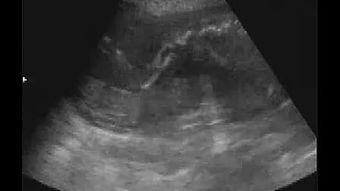

胚胎视频,顾名思义,就是通过高科技手段拍摄到的胚胎发育过程。这些视频让我们得以一窥生命的奥秘,感受生命的顽强与美好。

近年来,随着医学技术的不断发展,胚胎视频逐渐走进了人们的视野。通过这些视频,我们可以清晰地看到胚胎从受精卵到胚胎发育成胚胎的过程。每一个细节都让人惊叹不已,仿佛在观看一部生命的史诗。

胚胎视频让我们见证了生命的奇迹。从受精卵到胚胎,每一个阶段都充满了变化和挑战。